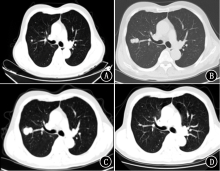

大多数肝癌患者发病时已为中晚期,且缺乏有效治疗手段,预后极差。本研究报道采用甲磺酸阿帕替尼联合卡瑞利珠单抗二线以上治疗1例原发性肝癌伴肺转移病例,取得了显著疗效,为晚期原发性肝癌的治疗提供了新的方法。